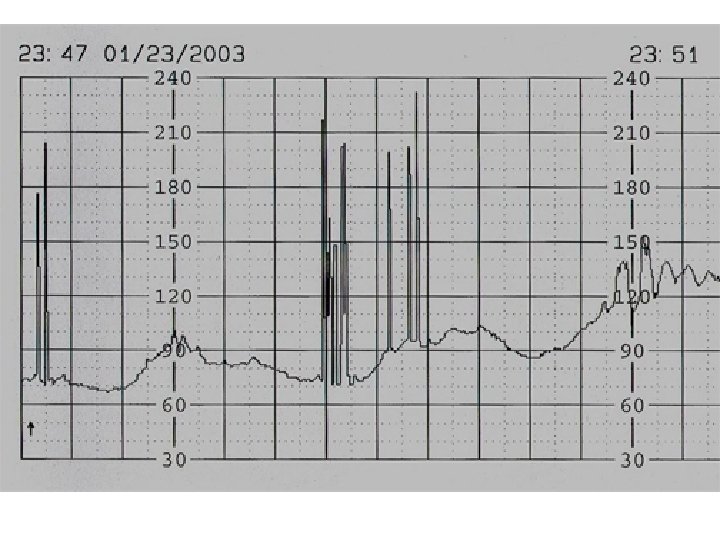

Interpretation of the Fetal Heart Tracing The interpretation of the fetal heart rate tracing should follow a systematic approach with a full qualitative and quantitative description of the following: • Baseline FHR rate variability • Periodic changes accelerations decelerations • Frequency and intensity of uterine contractions

Baseline variability The minor fluctuations in baseline FHR occuring at three to five cycles per minute. It is measured by estimating the difference in beats per minute between the highest peak and lowest trough of fluctuation in a one-minute segment of the trace.

FHR Variability Absent variability = Amplitude range undetectable Minimal = < 5 BPM Moderate = 6 to 25 BPM Marked = > 25 BPM

Sinusoidal and Pseudosinusoidal Patterns Sinusoidal pattern: A smooth, undulating pattern, lasting at least 10 minutes with a fixed period of three to five cycles per minute and an amplitude of 5 -15 bpm. Pseudosinusoidal: Usually caused by drugs such as Nubain or Stadol.